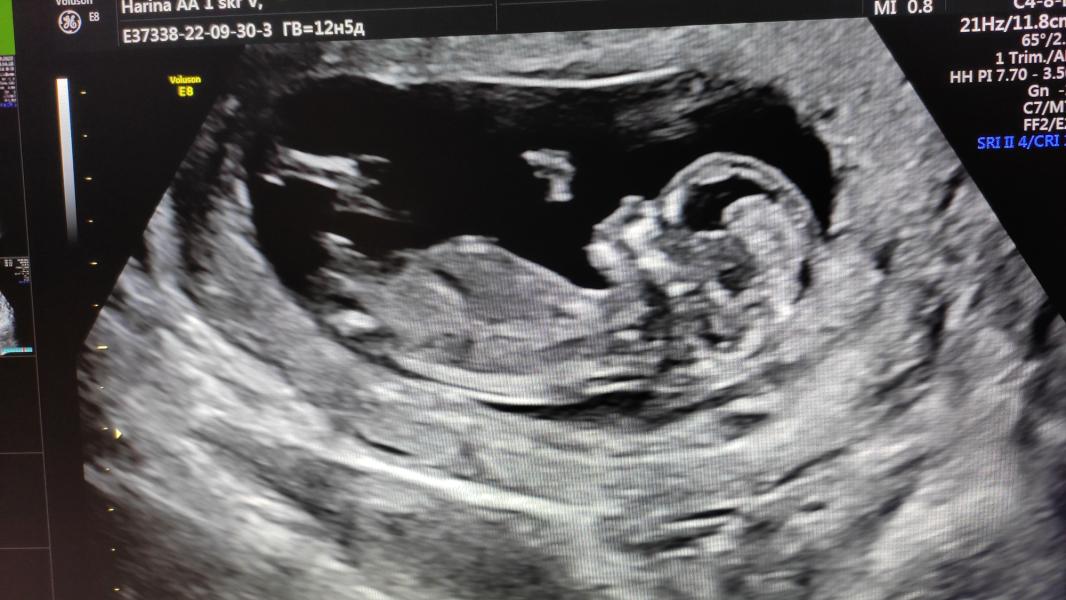

Первый скрининг❤️

От звука сердцебиения слезы сами по себе текут

Главное сердечко бьется и всё хорошо)